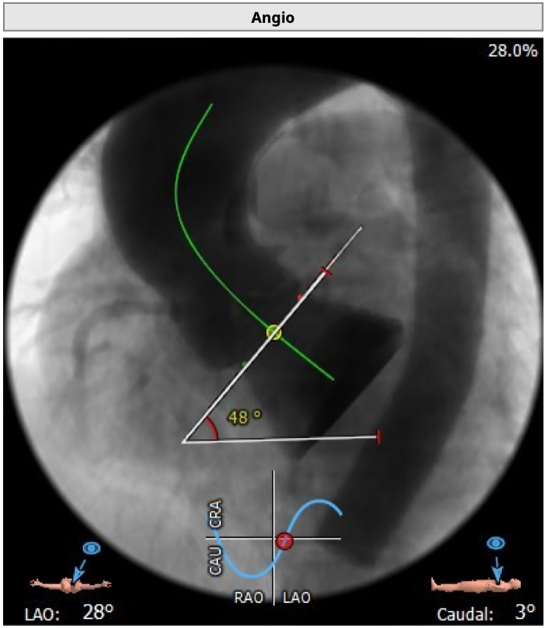

瓣环水平夹角48度。

主动脉根部造影